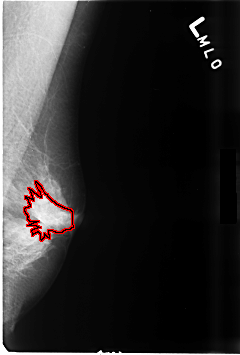

FILE: B_3480_1.LEFT_MLO.OVERLAY

TOTAL_ABNORMALITIES 1

ABNORMALITY 1

LESION_TYPE MASS SHAPE ARCHITECTURAL_DISTORTION MARGINS ILL_DEFINED

ASSESSMENT 3

SUBTLETY 3

PATHOLOGY BENIGN_WITHOUT_CALLBACK

TOTAL_OUTLINES 1

BOUNDARY